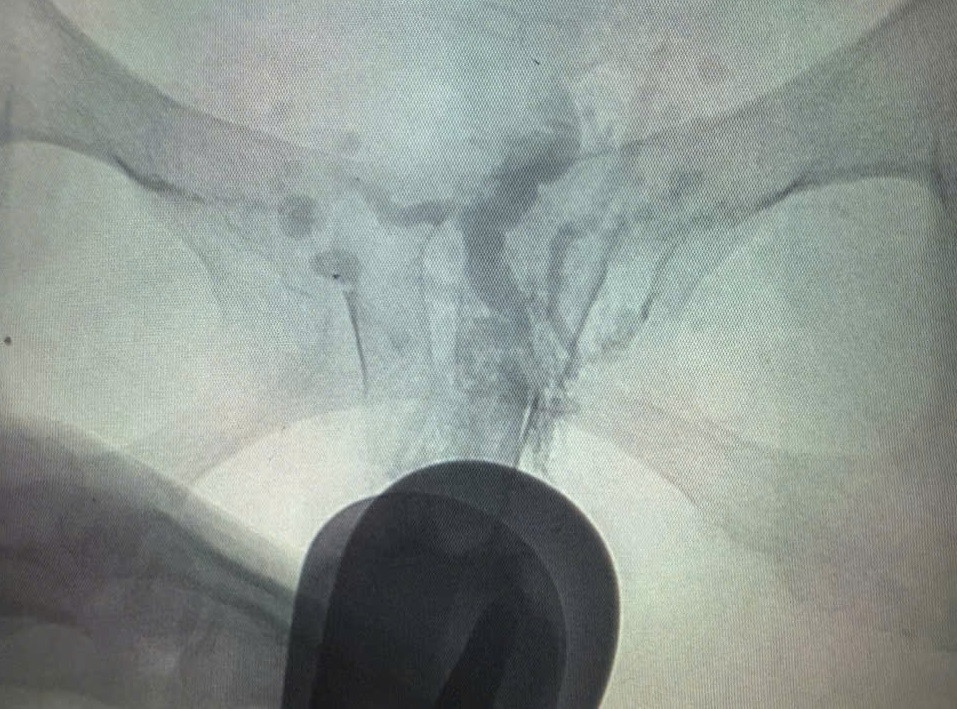

| Vị trí mạch máu dị dạng của bệnh nhân trên hình ảnh X-quang xóa nền |

Thời điểm trước khi đến Bệnh viện Nhân Dân Gia Định, nữ bệnh nhân bị xuất huyết âm đạo ào ạt, đe dọa tính mạng. Sau khi tiếp nhận người bệnh, các bác sĩ đã thăm khám và thực hiện các kiểm tra hình ảnh chuyên sâu. Kết quả MRI cho thấy, bệnh nhân bị dị dạng mạch máu vùng chậu và âm hộ, âm đạo.

TS.BS Nguyễn Đình Luân, Phó trưởng khoa Chẩn đoán Hình ảnh, người trực tiếp điều trị bệnh nhân cho biết: “Khi tôi đặt mỏ vịt thì thấy một búi mạch máu ngoằn ngoèo ở thành trái âm đạo của người bệnh có màu tím giống như chùm nho. Sau khi luồn kim dưới hướng dẫn của X-quang xoá nền, tôi thấy thuốc tương phản lan ra đúng như đám tĩnh mạch dị dạng nên quyết định tiến hành tiêm xơ hoá”. Ngay sau khi can thiệp, âm đạo của bệnh nhân đã được cầm máu hoàn toàn. Bệnh nhân đã hết đau, sức khỏe nhanh chóng bình phục.